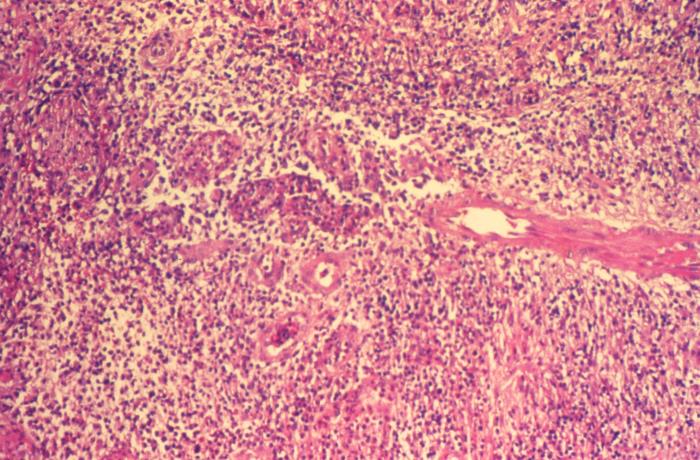

El portal Medline Plus detalla que el granuloma inguinal es una enfermedad de transmisión sexual causada por la bacteria Klebsiella granulomatis.

La enfermedad se manifiesta a través de úlceras en las zonas genital, perianal y anal que desgastan la piel ya que destruye el tejido genital; como si la bacteria comiera la carne de la zona afectada. Dichas protuberancias carnosas podrían llegar a ser indoloras, pero al ser lesionadas sangran con facilidad.

Es importante señalar que Medline Plus informa que en sus etapas iniciales puede confundirse con el chancroide; de igual forma, en etapas avanzadas se asemeja a "cánceres genitales avanzados, al linfogranuloma venéreo y a la amebiasis cutánea anogenital".